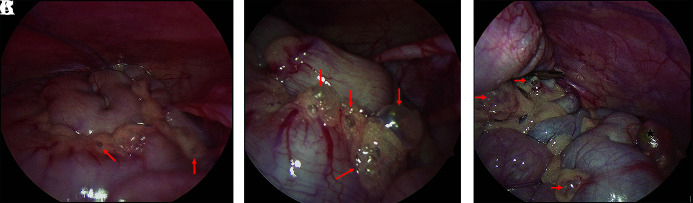

Pneumoperitoneum in infancy raises concern for visceral perforation and resultant urgent surgical exploration. However, benign pneumoperitoneum-defined as free intraperitoneal air without gastrointestinal perforation-can occur rarely, especially in infants with chronic ventilatory dependence. We present an unusual case of an 8-month-old infant with severe bronchopulmonary dysplasia (BPD), tracheostomy, and gastrostomy-tube dependence, with radiographic evidence of pneumatosis intestinalis and free intraperitoneal air. Diagnostic laparoscopy was performed which identified air within the mesentery of the small and large intestine, without evidence of true pneumatosis, perforation, inflammation, or ischemia. The patient recovered from their surgery uneventfully without any complications. This case highlights the importance of recognizing benign pneumoperitoneum, particularly in medically complex ventilator-dependent pediatric patients, and emphasizes the role of diagnostic laparoscopy as a valuable tool to confirm bowel integrity, preventing unnecessary laparotomy.